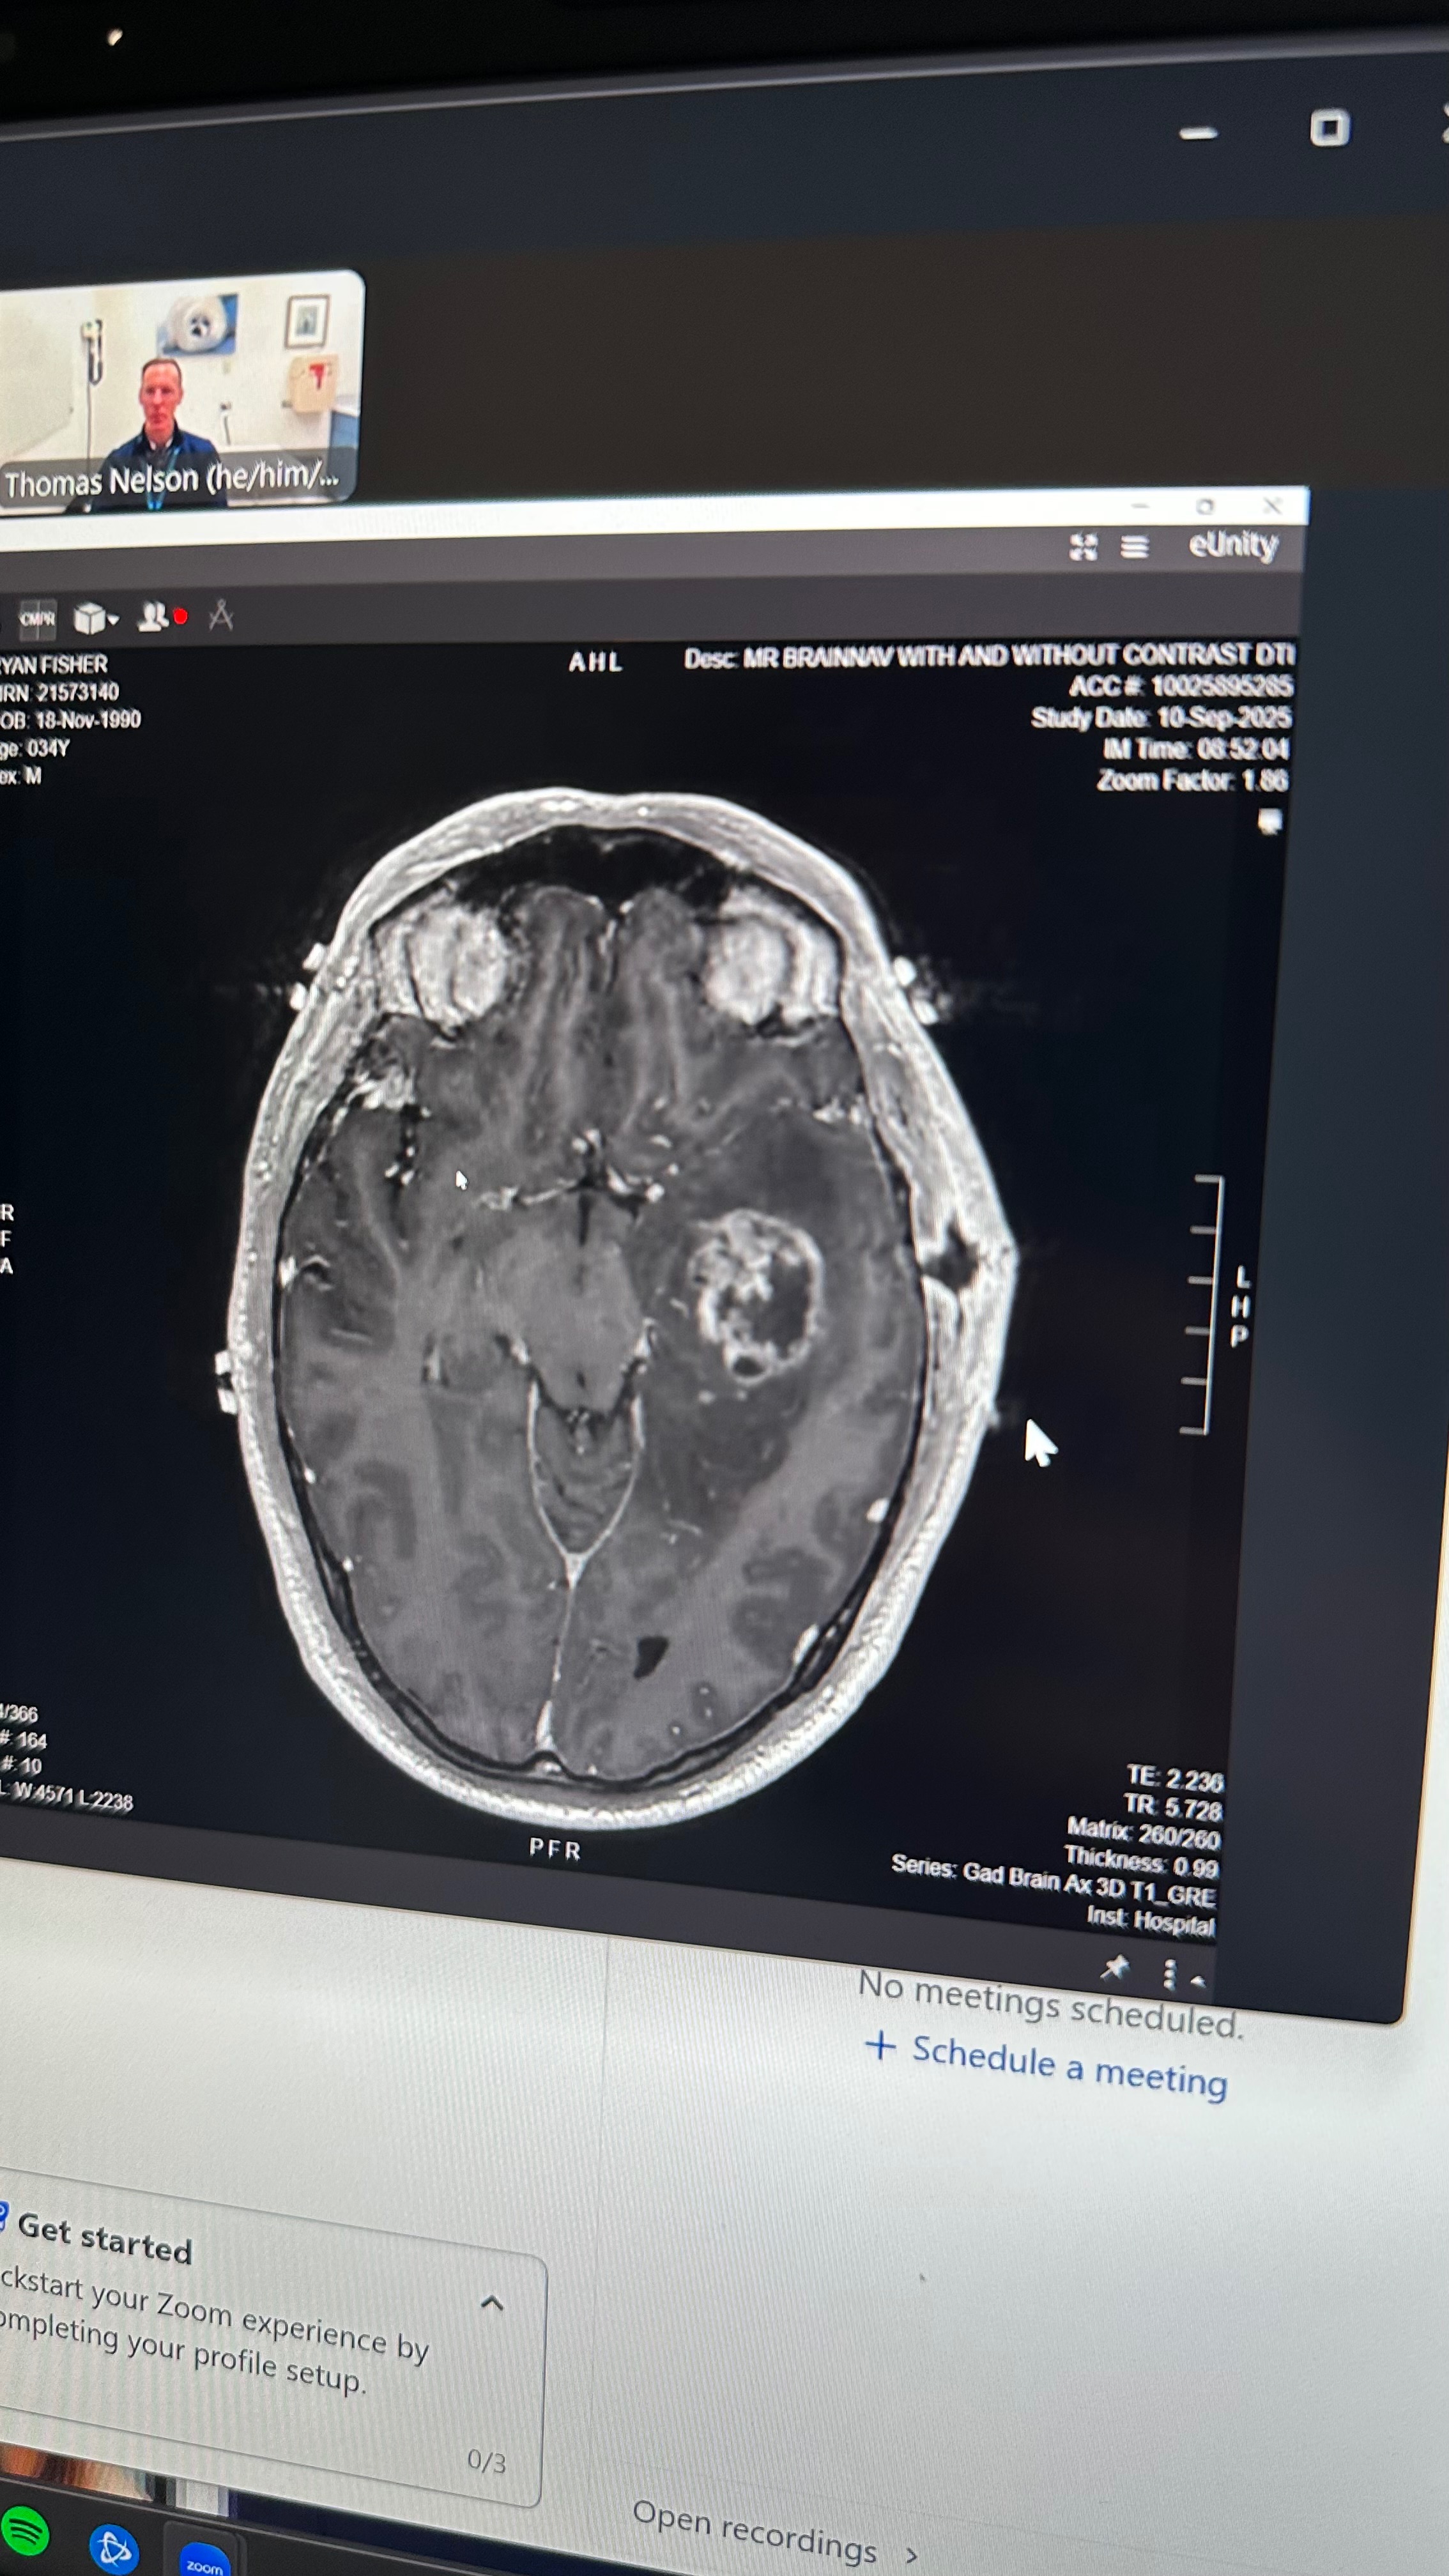

Just a few weeks ago, Ryan began experiencing severe migraines. He assumed it was from the long 8hour days in the sun. But on Friday, 8/29, the pain became unbearable, and Ryan went to the ER. There, doctors discovered a lime-sized tumor in the front of his brain.

With the support of family and friends, he connected with Dr. Mitchel Berger at UCSF, one of the top brain surgeons in the country. Dr. Berger saw his MRIs and immediately wanted to operate, within 3 days, Ryan bravely underwent an eight-hour craniotomy in San Francisco fully awake, giving him the best chance possible. The surgery was successful and they were able to retrieve all the enhancing tumor and only a tiny portion of non-enhancing cells were left.